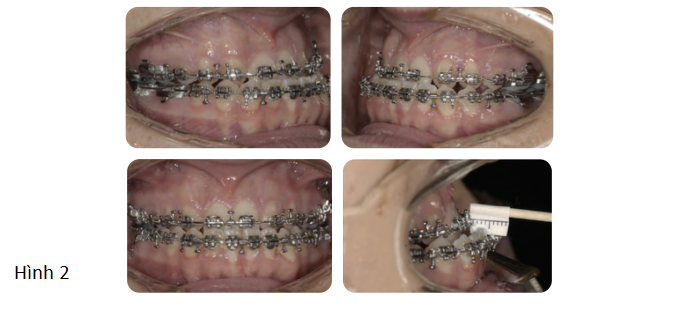

- Làm đều và làm phẳng các cung răng: Dàn đều răng bằng cách sử dụng dây cung đàn hồi ở thời điểm bắt đầu chỉnh nha tiền phẫu thuật. Làm phẳng cung răng thực hiện chủ yếu bằng dây cung SS (thép không gỉ).

- Phối hợp 2 cung răng: Đánh giá sự phối hợp 2 cung răng trong tương lai được thực hiện thông qua mẫu hàm nghiên cứu trước điều trị. Trong trường hợp này, phần nong rộng cần thiết ở cung răng trên có thể đạt được nhờ sử dụng dây cung bằng thép không gỉ hình chữ nhật.

- Làm mất bù trừ: Trong trường hợp này, cần làm mất bù trừ của cung hàm trên và hàm dưới để tạo ra độ cắn chìa âm phù hợp trước phẫu thuật và cho phép các dịch chuyển phẫu thuật mong muốn để hoàn toàn thúc đẩy sự thay đổi mong muốn trên gương mặt.

Việc làm mất bù trừ của cung hàm trên đòi hỏi phải dựng trục nhóm răng trước hàm trên. Điều này đạt được bằng cách nhổ các răng cửa bên hàm trên có kích thước nhỏ để tạo ra khoảng trống thích hợp. Ở cung hàm dưới, việc làm mất bù trừ đạt được bằng cách làm nghiêng ngoài các răng cửa hàm dưới.

- Duy trì đường giữa hàm dưới với đường giữa cằm: Trong trường hợp này, cung hàm dưới được điều trị không nhổ răng. Vì đường giữa hàm dưới trùng với cằm ở thời điểm bắt đầu chỉnh nha tiền phẫu thuật, nó được duy trì trong suốt giai đoạn làm phẳng và làm đều cung hàm dưới.